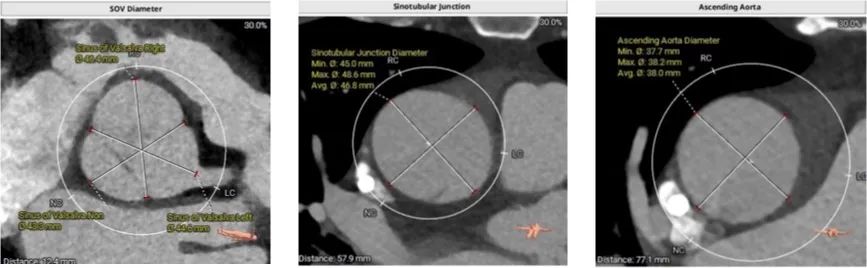

CT分析

患者主动脉瓣三叶式,瓣叶基本等大,窦部增宽,瓣叶不厚,瓣叶未见明显钙化;主动脉瓣环周长折算直径约28.3mm:

左室流出道平均直径30.7mm:

主动脉瓣环夹角56°:

左侧冠脉开口高度LCA 10.3mm,右侧冠脉开口高度RCA 20.8mm,左冠脉重度钙化,右冠脉前端支架:

术中造影角度LAO 13°,CAU 11°;主动脉弓、降主动脉及双侧髂总动脉散在钙化,主动脉弓、腹主动脉局部管壁增厚,腹主动脉局部管壁不规则;升主动脉夹层、窦管交界增宽。